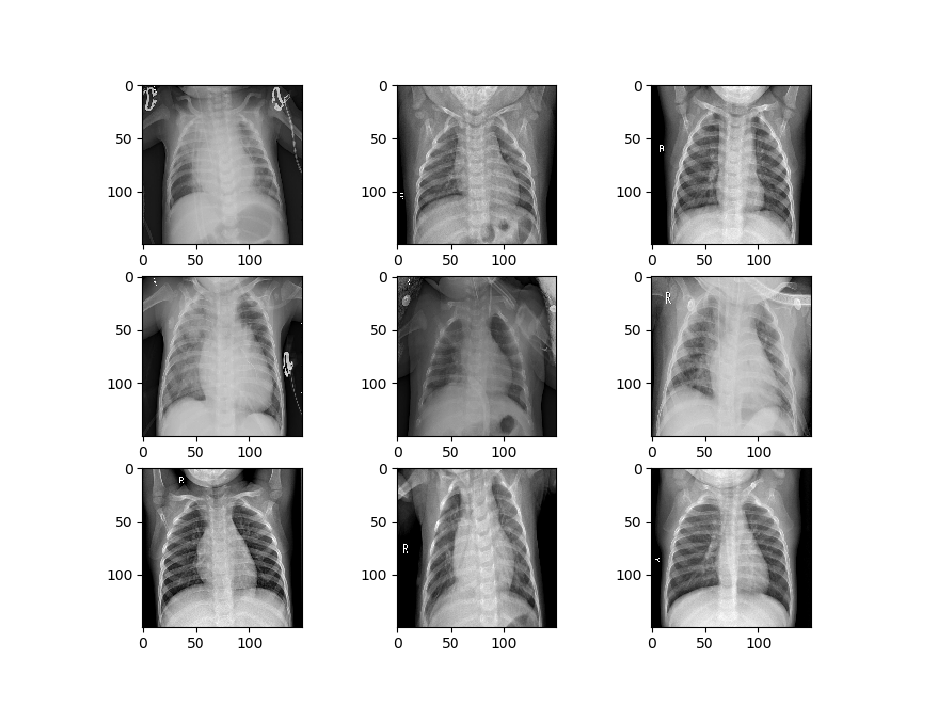

Let’s visualize some of the data to get a better idea of how the datasets will differ. First, we’ll visualize the data that is being used to train the first model.

image_show(train_generator_1)

Now we’ll visualize the second set of data.